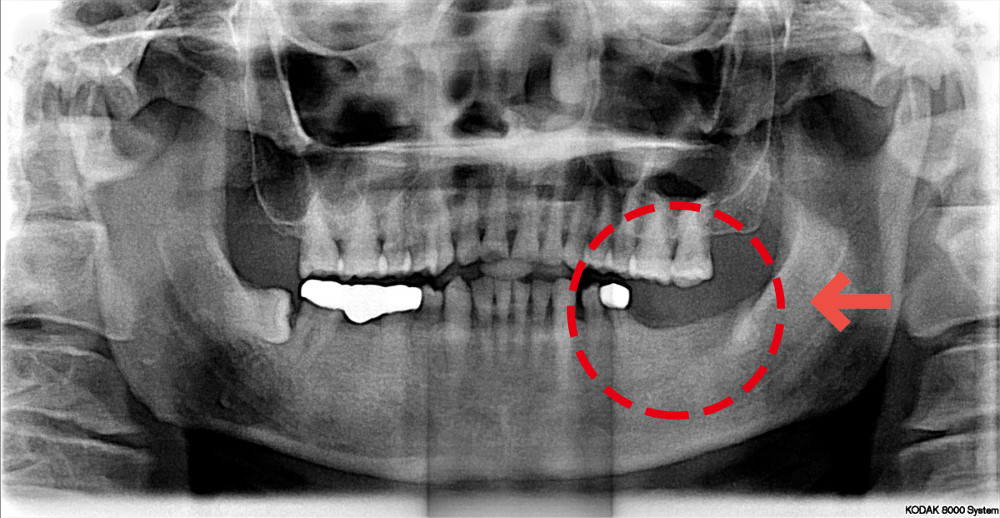

▲數位照片顯示缺牙位置:左下第一大臼齒、左下第二大臼齒